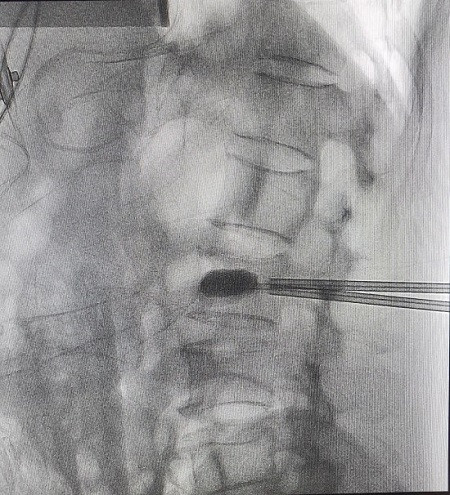

| Các bác sĩ thực hiện bơm xi măng trên máy DSA |

Nhóm phẫu thuật đã tiến hành can thiệp bơm xi măng tạo hình thân đốt sống L2 cho bệnh nhân Cương bằng hệ thống bơm bóng Ball Kyphoplasty (BKP) dưới hướng dẫn của hệ thống máy DSA. Chỉ một ngày sau can thiệp bằng phương pháp hiện đại này, bệnh nhân đã có thể ngồi, đi lại được.